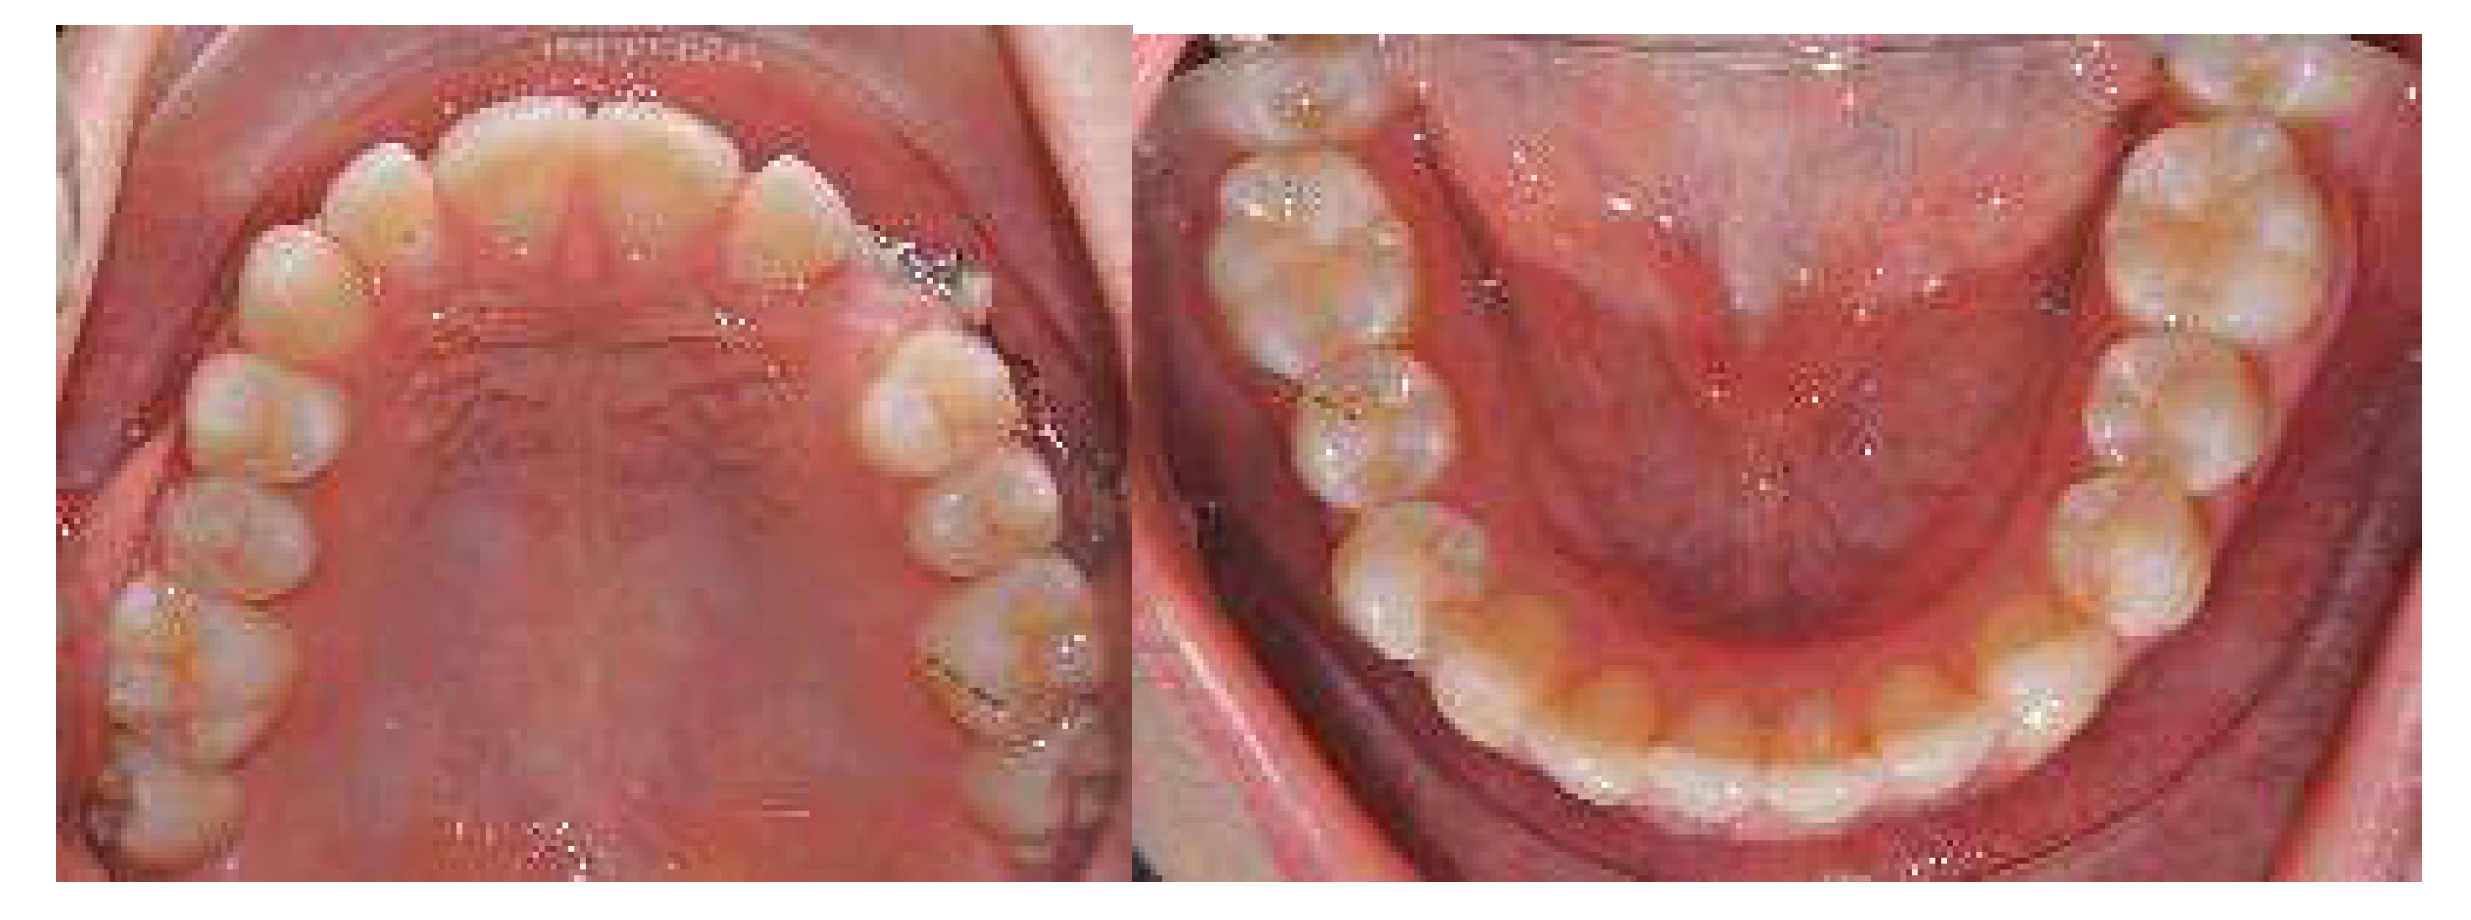

In the first Clincheck®, the use of an eruption compensator was planned in order to locate the displaced canine.

At the same time, the canine was linked to the button cutout of 36 teeth by using Class II elastics to extrude and tip it. On the right side, Class II elastics were placed in order to improve the dental Class II malocclusion (Figure 14 and Figure 15)

Figure 14.

First Clincheck® and the first set of aligners to create space and achieve the alignment and levelling of both arches. Use of elastics and buttons as auxiliaries to promote the extrusion of the impacted canine.

Figure 15.

Progress of treatment with the mechanics of elastics.

Once the displaced tooth was in a better position and near the crest, intraoral impressions and a new series of pictures were taken. Then, an upper arch expansion was planned in order to correct the transverse discrepancy and crowding.

A horizontal rectangular attachment was placed on the buccal surface of the canine, and lingual root torque was applied to ensure the three-dimensional control of the tooth movement (Figure 16).

Digital impressions after the first set of aligners and a new Clincheck® to refine the occlusion.